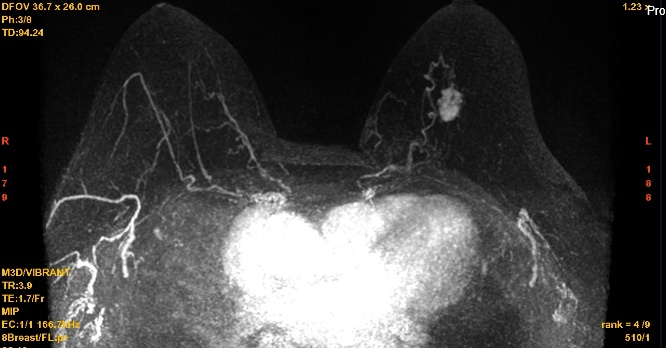

建议提前进行筛查(40岁前);筛查间期推荐每半年1次的临床体检和每年1次的乳腺x线检查及B超检查;必要时可缩短x线筛查的间隔时间,并增加乳腺MRI检查。